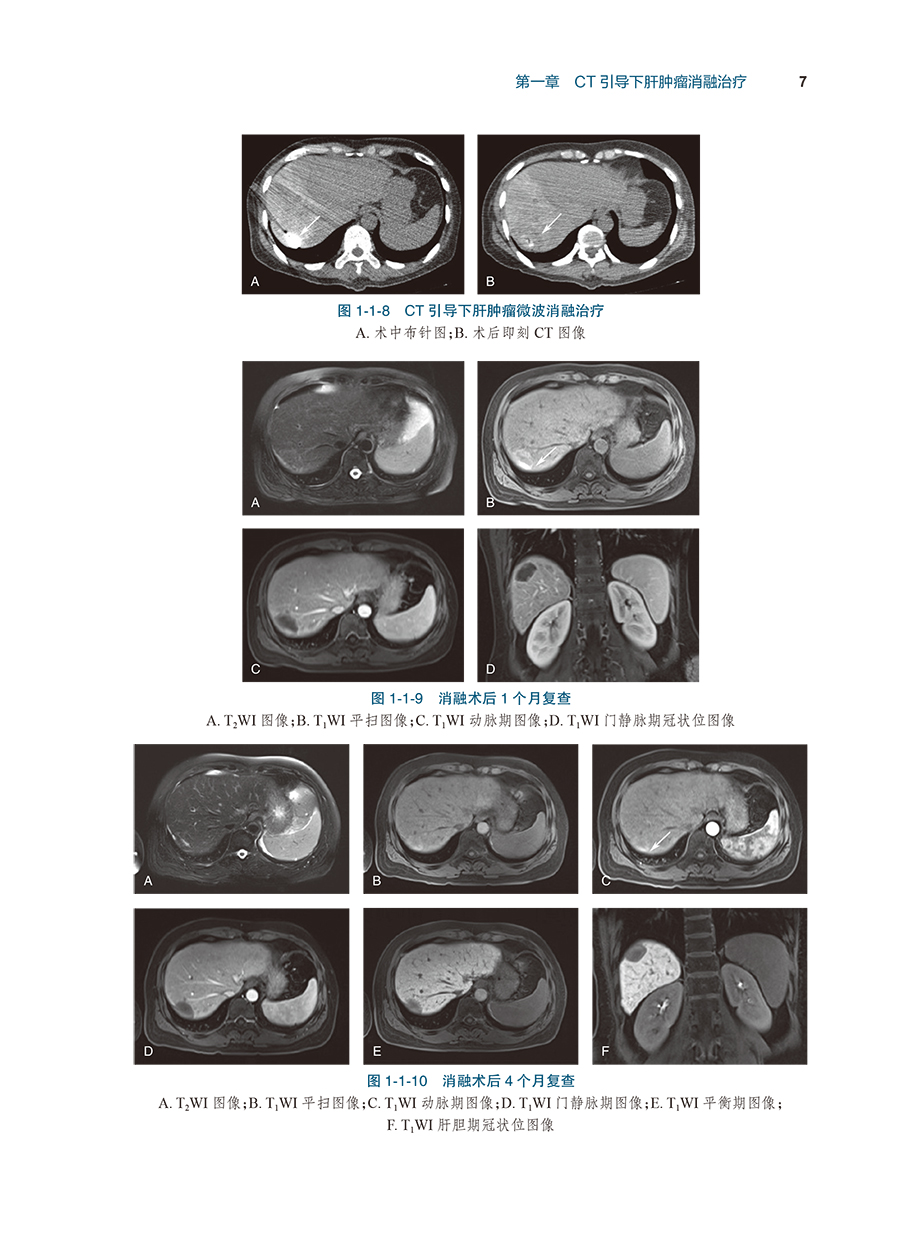

病例2TAE碘油标记后序贯微波消融治疗小肝癌/4

病例3肝包膜下小肝癌的微波消融治疗/8